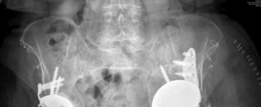

Anteroposterior (AP) pelvis:

Demonstrated significant superior and medial migration of the left acetabular component with evident periacetabular osteolysis. Lucency lines exceeding 2mm were observed at multiple interfaces, particularly zones 1 and 3 of DeLee and Charnley. There was evidence of prior bulk allograft incorporation, but with signs of partial resorption and failure to fully integrate into the host bone in areas of stress shielding. The femoral component appeared well-fixed in comparison.

Lateral hip (true lateral or cross-table lateral):

Provided further insight into the anteroposterior extent of component migration and bone loss. The superior migration was particularly pronounced, leading to significant disruption of the acetabular tear drop and potential intrapelvic protrusion if not contained.

Judet views (Obturator oblique and Iliac oblique):

These specialized views were crucial for detailed assessment of the anterior and posterior columns and walls of the acetabulum. The obturator oblique view highlighted significant superior and posterior column erosion, while the iliac oblique view showed extensive destruction of the superior acetabular dome and a large contained defect superiorly, consistent with substantial Paprosky type IIIb bone loss, potentially extending to type IV.